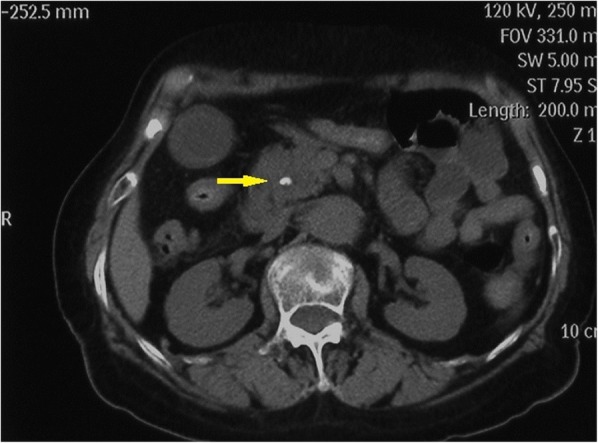

A 75-year-old woman was admitted to the hospital with abdominal pain, nausea and vomiting for 3 days. She did not drink alcohol, and there was no clinical or biochemical evidence of primary liver disease or coagulopathy. Physical examination revealed mild tenderness in the right upper abdominal quadrant. Laboratory tests revealed that the percentage of neutrophils (N%) was 80.3% (50–70%), alanine aminotransferase (ALT) was 192 U/L (< 64 U/L), aspartate aminotransferase (AST) was 66 U/L (< 64 U/L), γ-glutamyl transpeptidase (γ-GT) was 197 U/L (< 47 U/L), and all other laboratory parameters were normal (e.g., haemoglobin and platelet counts, prothrombin time, and renal function). An abdominal computerized tomography (CT) scan demonstrated dilatation of the extrahepatic bile duct with a stone at the lower CBD and sludge in the gallbladder. (Fig. 1) Bile duct cholangiopancreatography revealed a dilated CBD (10 mm in diameter) with a round filling defect (8 mm in diameter) (Fig. 2). Balloon dilation (10 mm in diameter) of terminal CBD after a 5-mm long sphincterotomy for extraction of the stone was uneventful. Unfortunately, she presented with cholangitis and a significant increase in the percentage of neutrophils (94%) and cholestatic parameters (total bilirubin 111.1 μmol/L (2–18 μmol/L), direct bilirubin 81.3 μmol/L (< 7 μmol/L), ALT 465 U/L, AST 538 U/L, and γ-GT 634 U/L) after 3 days.